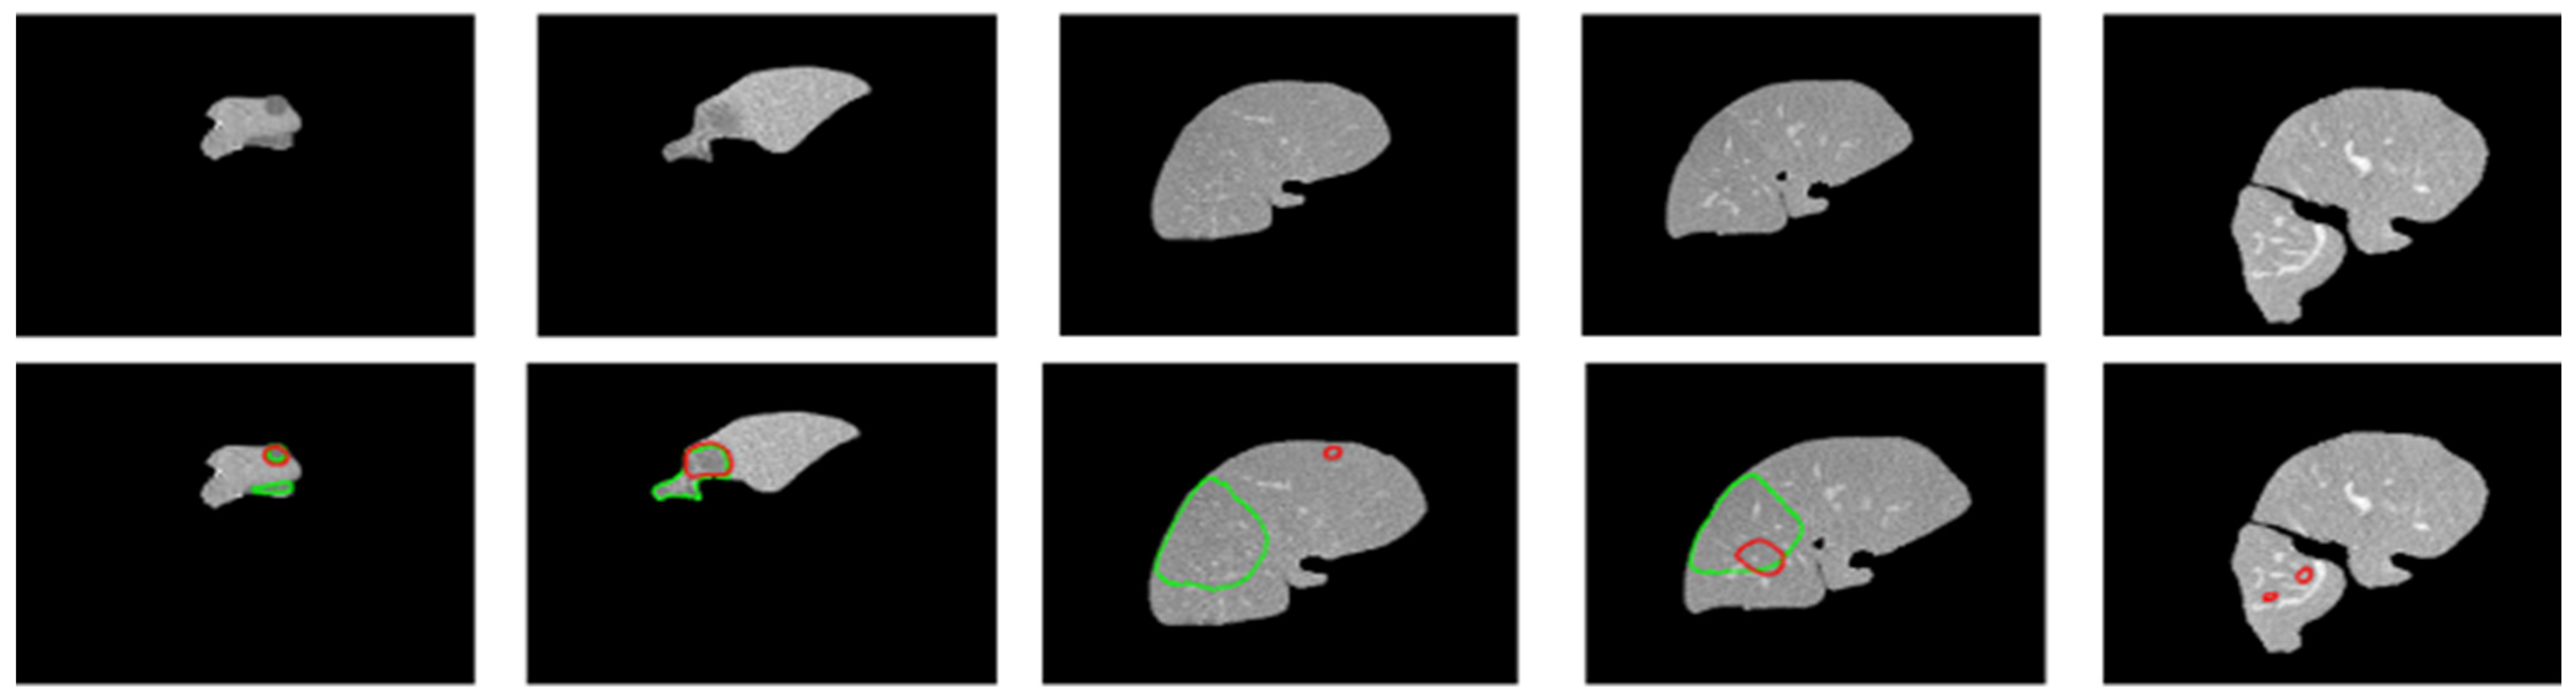

Figure 6 shows the performance comparison of different tumor segmentation networks, where the red boundary represents the predicted pixels. Figure 7 and Figure 8 show the mask overlay of ground truth and the predicted mask of the liver and tumor for the samples. The second rows in Figure 7 and Figure 8 show the regions highlighted with red and green boundaries. These borders indicate the incorrect interpretations of the models in the case of liver and tumor prediction. The green boundaries indicate the actual liver and tumor locations in the image, while the red boundaries highlight the model-predicted liver and tumor regions. As a result, this misinterpretation of the models, which predicted the incorrect liver and tumor locations, did not contribute to the dice score, affecting the overall dice score for both the liver and tumor.

Figure 7. Original images are shown in the first row. The second row shows the boundaries of the ground truth and predicted liver images laid over each other. The green boundary shows the ground truth while the red boundary shows the predicted pixels.

Figure 8. The first row shows the original images. The second row shows the boundaries of the ground truth and predicted tumor images laid over each other. The green boundary shows the ground truth pixels whereas the red boundary shows the predicted pixels.